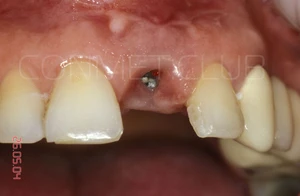

Вид на лунку удаленного зуба. Щипцы при удалении не использовались, только кюретажная ложка СМ 2/4 и прямой элеватор.

Сразу после экстракции зуба 21 производится установка имплантата КОНМЕТ с полированной трансгингивальной частью высотой более 3 мм. Интерфейс имплантата - просто конус Морзе и ни каких антиротационных шестигранников!

Имплантат установлен и зафиксирован винт-заглушка. Обратите внимание, что даже при столь широком экваторе имплантата не удалось полностью перекрыть диаметр костной альвеолы в направление зуба 11. Швы не накладывались и поверхность имплантата закрывалась мазью Солкосерил Дентал